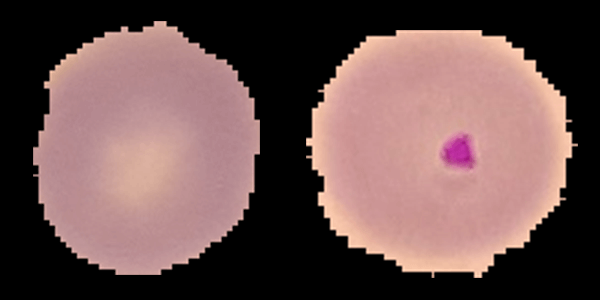

Biomedical & Health Fields

Explore real-world examples and industry use cases of Wolfram technologies in biomedical & health fields. Contact Wolfram about your industry.Blog